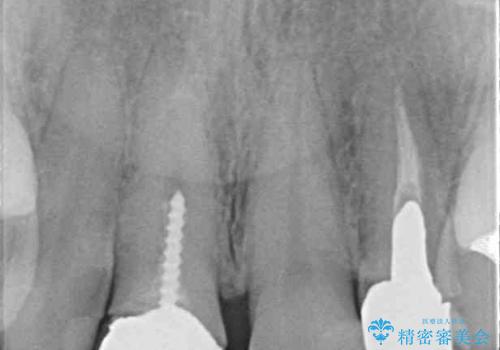

- 保険診療でのクラウンが変色してしまったとのことで来院された患者様です。

根管治療がされていなかったため、まずは根管治療を行い、その後オールセラミッククラウンにて補綴することとしました。